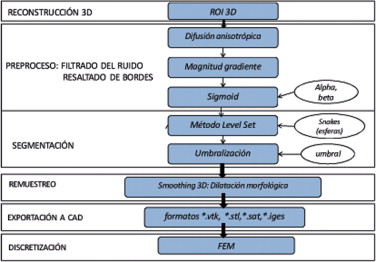

El problema de obtener modelos geométricos a partir de imágenes médicas implica la utilización de un conjunto de rutinas de procesamiento aplicadas a la matriz 3D de las imágenes médicas a lo largo de varias etapas de procesamiento. En la figura 1 se observan las cinco etapas propuestas con las herramientas de software utilizadas en cada una de ellas, las cuales son: (1) etapa de lectura y reconstrucción, en la cual se implementó una rutina para obtener una imagen 3D de dimensiones m × n × o obtenida por el apilamiento paralelo de o cortes ortogonales (axial, coronal o sagital) del mismo tamaño de m × n pixels , donde cada elemento de la matriz representa un valor de intensidad de gris calculado por la interacción de la radiación en el tejido. (2) Preproceso, en la cual se aplicaron rutinas de suavizado de ruido y realzado de bordes, de este modo se mejoró la calidad de las imágenes, preparándolas para la siguiente etapa. (3) Segmentación, en la cual se utilizaron rutinas de extracción del volumen de los tejidos u órganos de interés. (4) Remuestreo, donde se emplearon rutinas de posprocesamiento para suavizar las superficies y eliminar elementos no conectados presentes en los volúmenes segmentados. (5) Exportación de modelos, para lo cual se implementaron rutinas para almacenar los volúmenes obtenidos en formatos legibles por herramientas de visualización médica y CAD, en las cuales se visualice en sólidos, superficies, mallas, etc.

Figura 1. Esquema de procesos y rutinas implementados en una herramienta de procesamiento de imágenes médicas desarrollada en MATLAB [13] . |

Para la obtención de los modelos geométricos y la interacción con los algoritmos de procesamiento considerados en este trabajo, se desarrolló una herramienta computacional [13] bajo la plataforma de MATLAB [12] , en la cual se integraron las rutinas por etapas (fig. 1 ).

Las rutinas presentadas en el apartado anterior fueron aplicadas en imágenes médicas, orientados por flujogramas de algoritmos establecidos para las etapas representadas en la figura 1 . A continuación presentamos los resultados obtenidos en cuatro casos de estudio.

Las IRM del ventrículo izquierdo se caracterizan porque la fuerza del gradiente en el endocardio es por lo general diferente a la del epicardio. Asimismo, el miocardio es fuertemente influenciado por inhomogeneidades en escala de grises responsables de los cambios locales en la media y la varianza de los tejidos. Considerando estas peculiaridades, es necesario utilizar más de una sola técnica en las etapas de preprocesado y segmentación. El flujograma de algoritmos utilizado es presentado en la figura 14 . Las técnicas son detalladas a continuación.

Figura 14. Flujograma para la obtención del modelo del ventrículo izquierdo. |